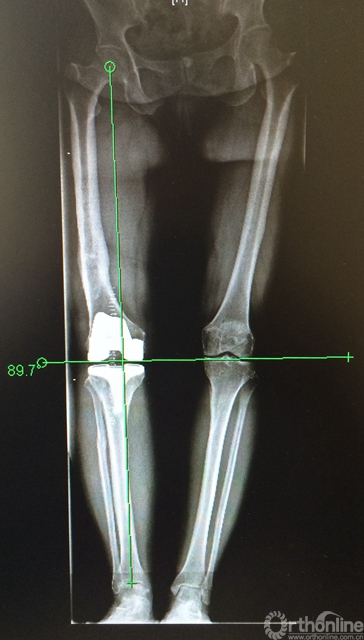

图1a. 双下肢全长片,右膝重度骨性关节炎,右股骨中下1/3陈旧骨折畸形愈合,向内侧成角畸形。

图1b. 右股骨中下段内侧成角畸形,股骨外翻角约14度。

图1c. 矢状位显示股骨中下段无明显成角畸形。

(2)畸形发生在冠状位,关节外股骨中下段;下肢全长片测量,股骨中下段内侧成角,股骨外翻角约14度(图1b);